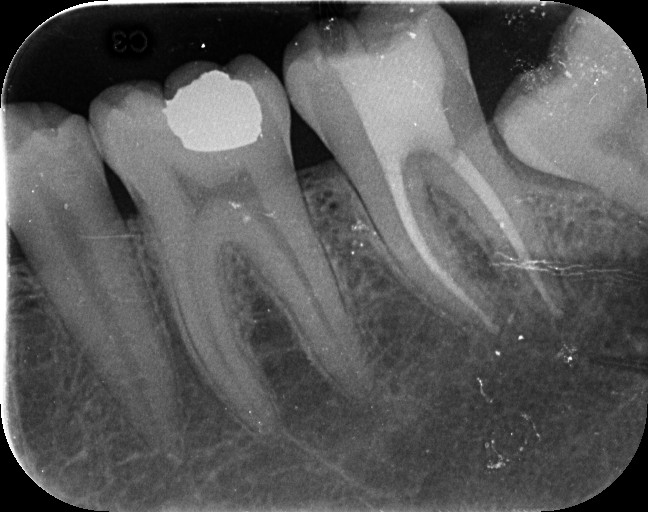

Also known as an apicoectomy, this procedure is performed when infection or inflammation persists at the tip of a tooth’s root, even after root canal treatment. We gently access the root end, remove the infected tissue, and seal the area to prevent future problems-all with the help of magnification and precision tools.

Unlike traditional techniques, our procedure is guided by high-powered dental microscopes, giving our specialists enhanced visibility into the smallest details. This level of precision helps us: